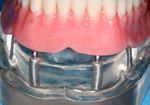

Overdentures

Bar overdenture

A cast bar of metal is secured to the implants. The complete denture then attaches to the bar with semiprecision attachments allowing no movement of the denture.

Ball overdenture

Ball and socket type attachments can be placed on implants and dentures to prevent most movement.